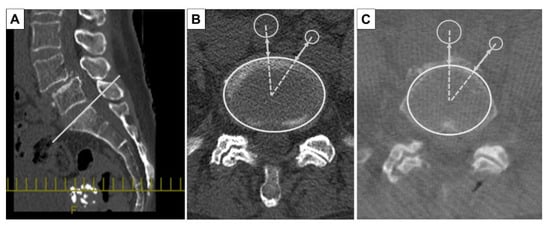

All patients underwent preoperative and intraoperative CT. The preoperative CT (Discovery CT750 HD, Revolution CT, GE Healthcare, Waukesha, WI, USA, WL: 300, WW: 1200) was performed with the patient in the supine position. The intraoperative CT (O-arm®, Medtronic Sofamor Daneck, Memphis, TN, USA) was performed with the patient in the prone position when spine surgeons inserted pedicle screws into the vertebral bodies. The preoperative and intraoperative CT images were analyzed with multi-planer reconstruction (MPR) Works software (GE Healthcare, Waukesha, WI, USA) to measure each level precisely. In the CT axial image, at the L4 pedicle, L4/5 disc, L5 pedicle, and L5/S1 disc level, we measured the shortest distance between the abdominal arteries (aorta or common iliac artery, internal iliac artery) and the vertebral body or intervertebral disc (SDA: shortest distance to the aorta) on a line connecting the center of the abdominal arteries and the vertebral body or intervertebral disc (Figure 1) [12]. The amount of abdominal arterial translation (AAT) during surgery was defined as “SDA on intraoperative CT” minus “SDA on preoperative CT”. In addition, the presence of aortic calcification, and the bifurcation level to the common iliac artery were evaluated in the preoperative CT axial images (Figure 2).

Figure 1.

Measurement method of computed tomography (CT) images. Multi-planer reconstruction (MPR) Works software (GE Healthcare) was used to measure the shortest distance between the abdominal arteries and the vertebral body or intervertebral disc (SDA) at each level. When measuring the disc level, the MPR line was positioned in the sagittal plane at the cranial endplate of the caudal vertebral body (A), a line was drawn to connect the center point of the disc with the center point of the artery, and the shortest distance (two-way arrow) between the anterior margin of the disc and the artery wall margin was measured. Preoperative CT (B) and intraoperative CT (C) images were analyzed at each level precisely.